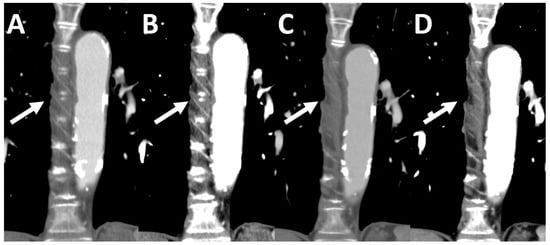

3.4. Subjective Image Quality